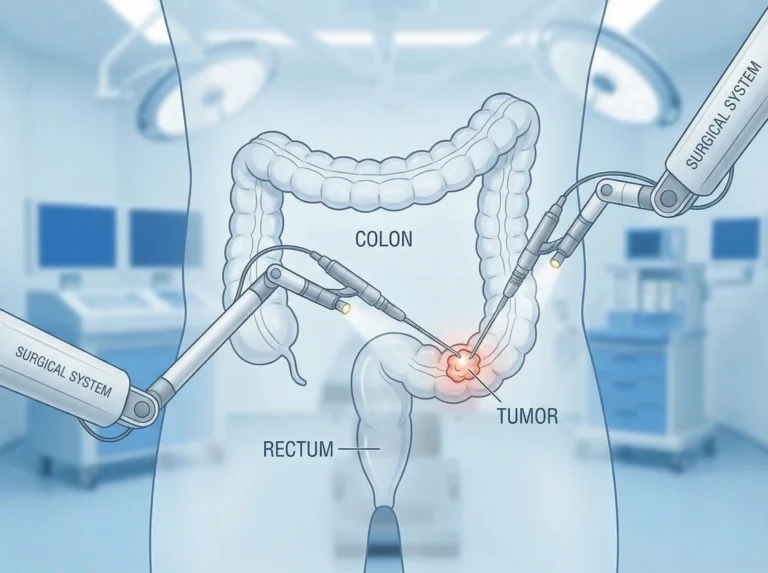

Introduction Colon cancer surgery in Mira Road, The Colon cancer is one of the most common types of cancer worldwide, and timely…

Best Colorectal Cancer Surgery In Mira Road Understanding What You’re Going Through Colorectal cancer surgery in Mira Road provides advanced treatment options.…

Introduction Minimally Invasive Cancer Surgery in Mira Road. Let’s understand, Cancer treatment has evolved dramatically over the past few decades, with surgical…

Why Choose Laparoscopic Cancer Surgery in Mira Road for Cancer Treatment Cancer treatment has evolved significantly over the past few decades, with…

Understanding What You’re Going Through If you or someone close to you has been diagnosed with colorectal cancer, it’s completely normal to feel…